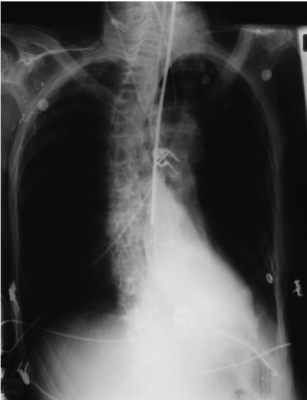

X quang ngực:

chụp trước khi rút nội khí quản (hình): Vẹo cột sống, xoay, căng phồng quá mức, không có tổn thương khu trú (hình)

2. Xem xét X quang của bệnh nhân này (Hình trên), bạn có thể nhìn thấy được thiết bị/dụng cụ theo dõi nào?

2. Xem xét X quang của bệnh nhân này (Hình), bạn có thể nhìn thấy được thiết bị/dụng cụ theo dõi nào?

- Các đầu đo ECG

- Ống nội khí quản và lò xo của van bơm hơi vòng bít

- Đường truyền trung tâm (tĩnh mạch cảnh trong bên phải)

- Đầu dò Doppler thực quản

- Ống thông mũi dạ dày

- Clip giải phóng hạch nách.